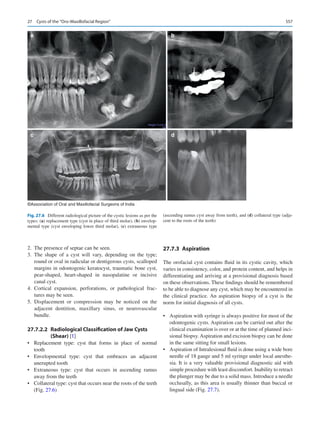

icine man for their healthcare. Direct to consumer marketing

of healthcare tools such as genetic testing is already preva-

lent in many countries. Several patients are aware of which

chemotherapy may be best effective for the management of

1  Oral and Maxillofacial Surgery in India: How Did We Get Here and Where Are We Going?

6

their cancers even before they see their doctor, today. Where

does that place a specialist in the future?

In a keynote address at the Royal College of Surgeons in

London at the 50th anniversary of the IAOMS, Brian Schmidt

DDS, MD, PhD, Director, Bluestone Center for Clinical

Research, and Professor of Oral and Maxillofacial Surgery at

New  York University pondered about the future of OMS

internationally. He emphasized three units of care that oral

and maxillofacial surgeons provide universally—

1.	 Management of maxillofacial trauma.